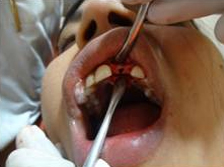

After Punch Cut

Placement of Bone Grafting

Drilling for Implant